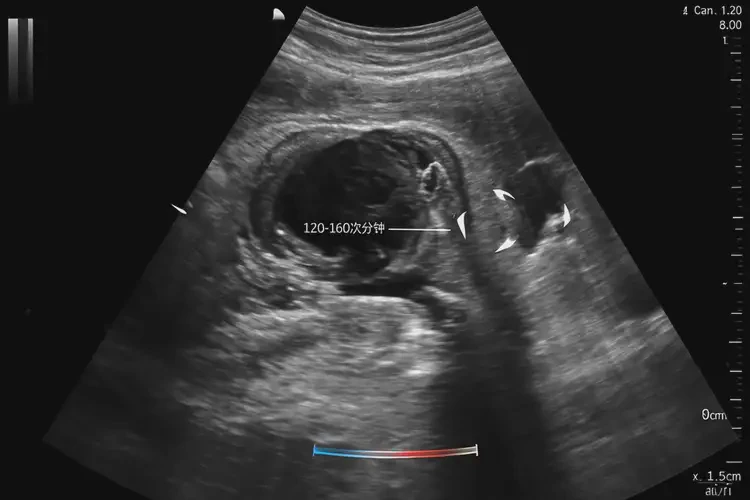

在正常情況下,懷孕80多天的胎兒胎心率應(yīng)該在120-160次/分鐘之間。胎心率低于120次/分鐘或高于160次/分鐘都可能表示胎兒存在健康問題。當(dāng)胎心率降至83次/分鐘時,這通常被視為胎兒心動過緩,可能表明胎兒的心臟功能存在問題或其他健康風(fēng)險。

懷孕80多天胎心率83寶寶還能要嗎(圖1)